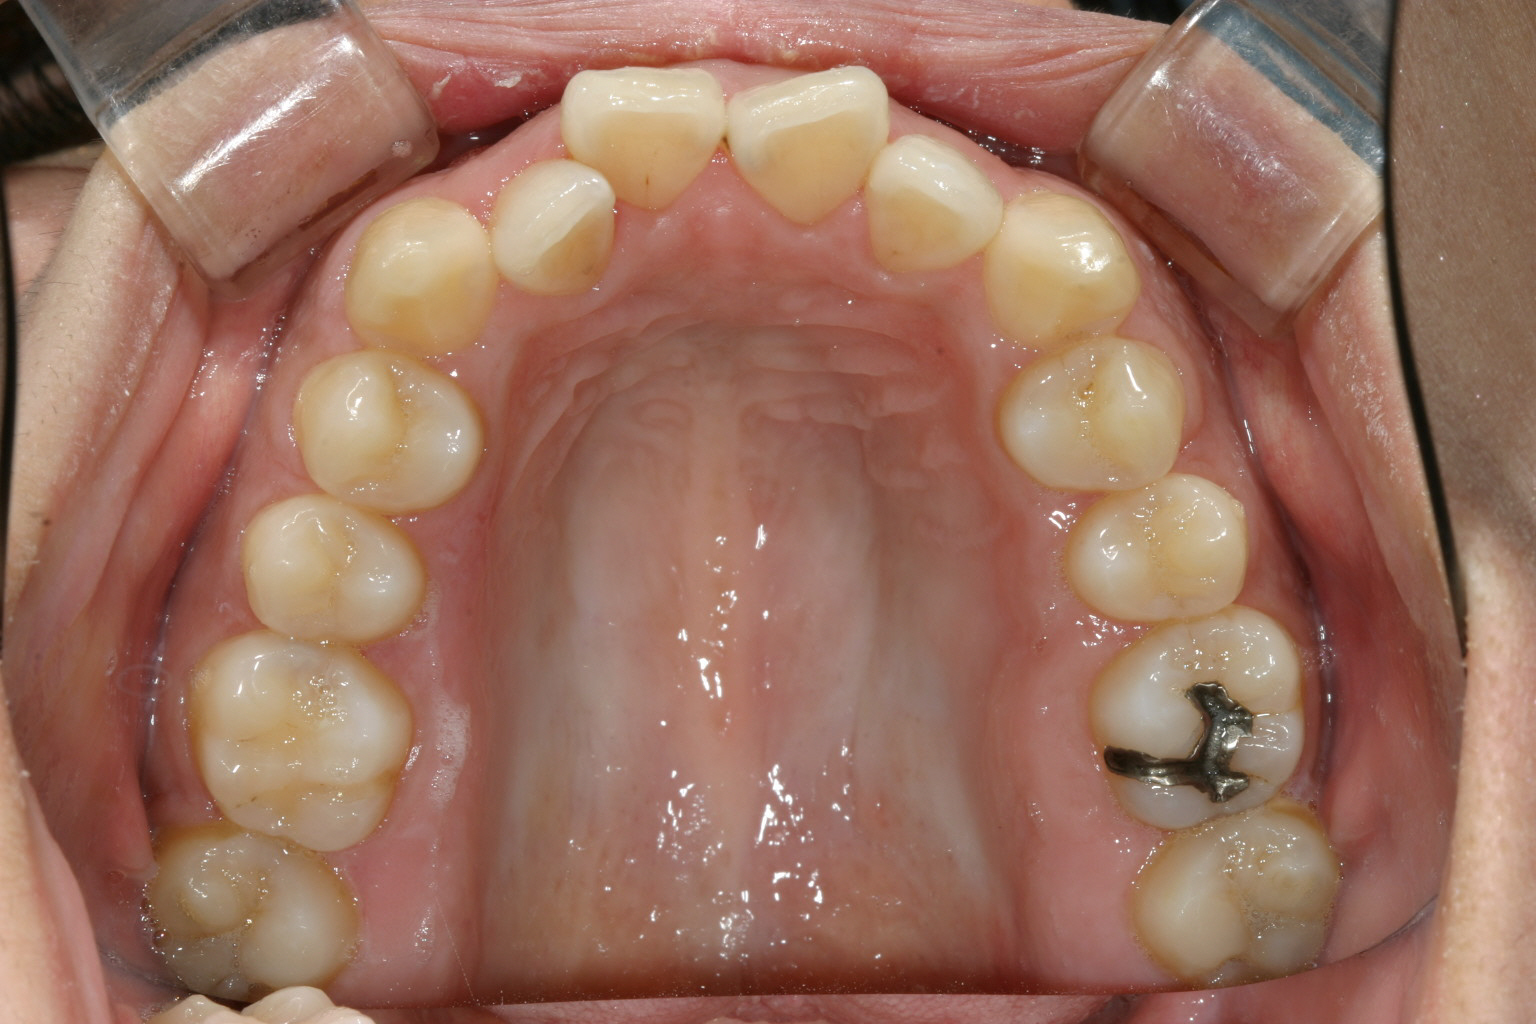

症面観です。 見栄えは悪いですが、ゆっくりとした力がかかるため歯には優しい装置です。

下顎もこんな感じです。綺麗でしょ?